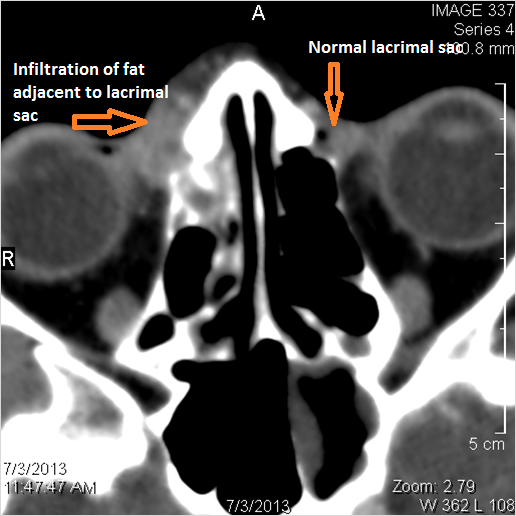

Nasal Cavity and Nasolacrimal Canal and Sac

There is  infiltration of the fat surrounding the nasolacrimal sac either preseptal or postseptal.